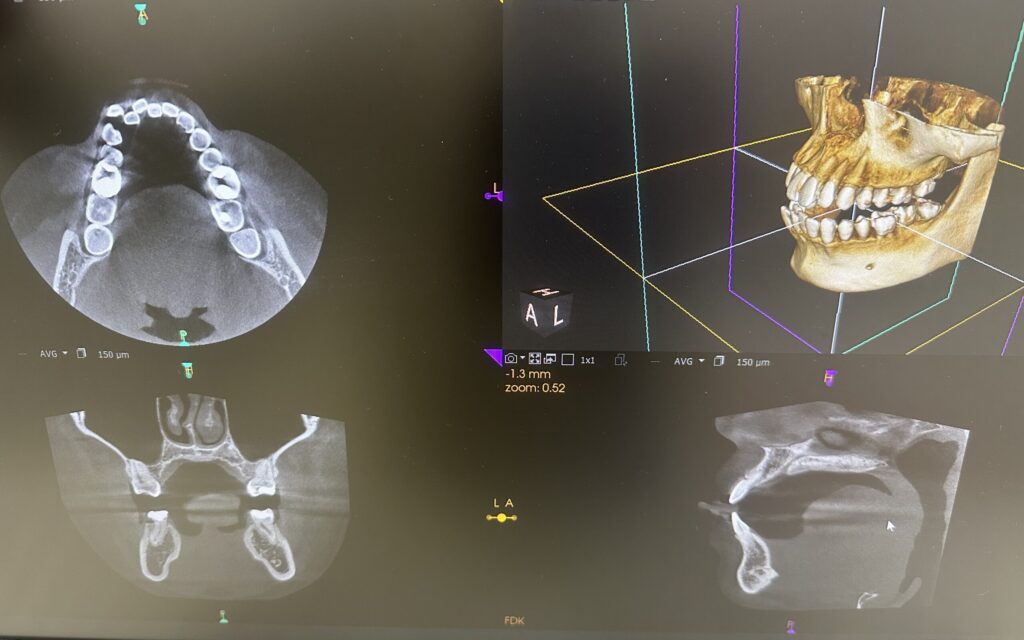

理想の角度が分かっても、土台となる骨の厚みが足りなければ無理な移動はできません。

CTを用いることで、3次元的に歯の根っこの位置と骨の厚みを確認します。

これにより、歯根を傷めるリスクを最小限に抑えつつ、安全に限界まで口元を下げるプランが作成可能になります。

無理に下げすぎると、かえって老けて見えたり、口元が寂しい印象になったりします。CTで骨の厚みを見ながら、安全かつ美しい限界点を探ります。 - 中高生の2期治療: